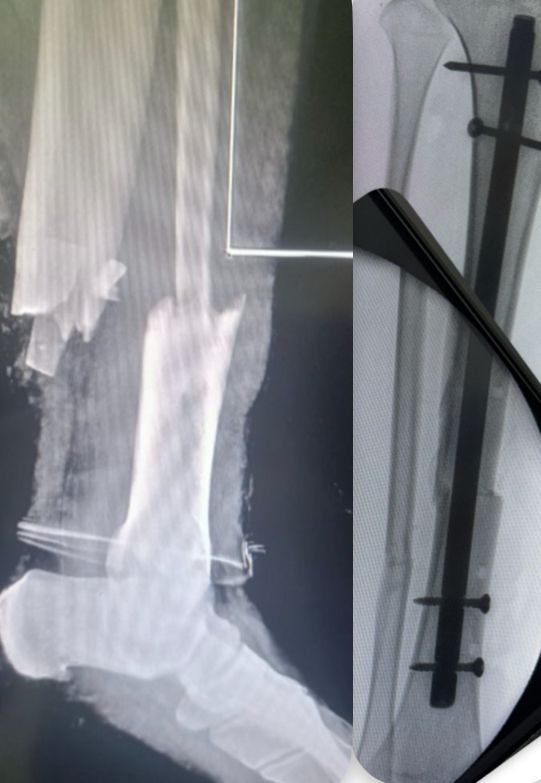

Fotos y videos

• Atención a fracturas

Ortopedista Desgaste articular-Fracturas-Lesiones deportivas